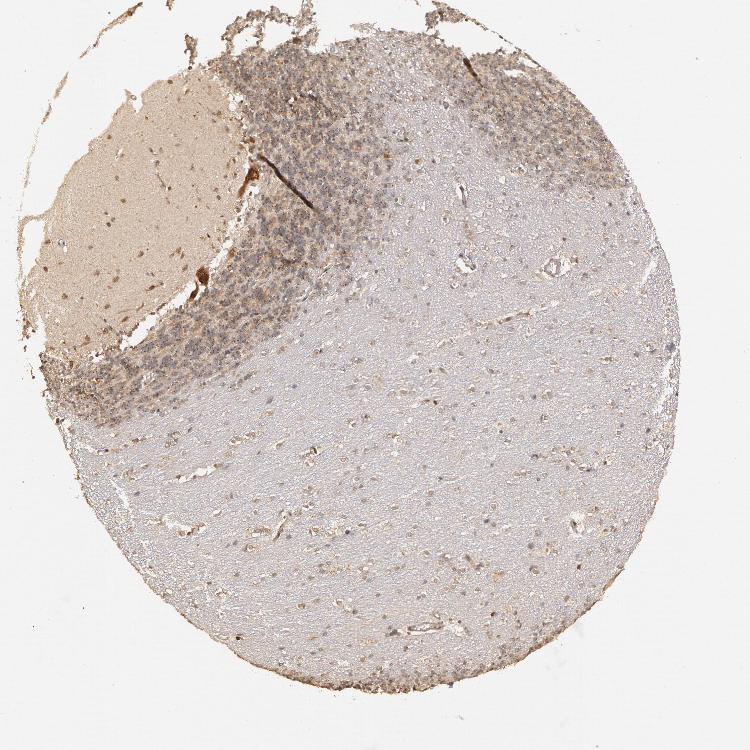

CEREBELLUM - Antibody stainingi

Antibody staining in the annotated cell types in the current human tissue is reported as not detected, low, medium, or high, based on conventional immunohistochemistry profiling in selected tissues. This score is based on the combination of the staining intensity and fraction of stained cells.

Each image is clickable and will lead to virtual microscopy that enables deeper exploration of all samples and also displays staining intensity scores, fraction scores and subcellular localization as well as patient and tissue information for each sample.

Antibody HPA001358

Purkinje cells High

Cells in granular layer Low

Cells in molecular layer Low